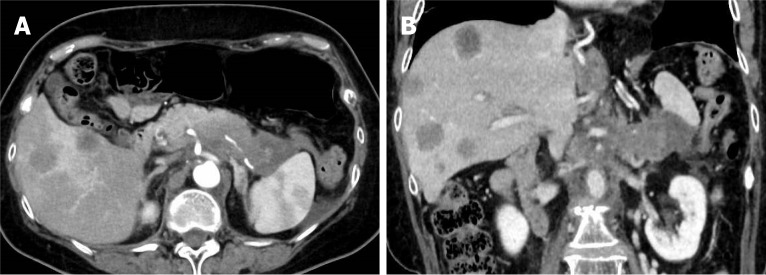

Case summary: A 74-year-old woman with pancreatic body and tail cancer developed fever and left-sided chest pain after multiple courses of chemotherapy. Computed tomography revealed fluid accumulation around the pancreatic tail and spleen along with a left pleural effusion. The effusion was diagnosed as reactive secondary to pancreatic fluid leakage. Endoscopic retrograde cholangiopancreatography identified irregular stenosis of the main pancreatic duct in the pancreatic body. Distal to the stenosis, the main ductal structure was nearly obliterated by the tumor. The contrast medium had leaked into the pancreatic fluid leakage area through several fine, disrupted ductal structures. The guidewire was successfully advanced through an extremely fine tract that was not the main contrast-filling route. Standard dilators failed to expand the rigid trans-tumoral tract. A second endoscopic retrograde cholangiopancreatography using a drill dilator successfully expanded the trans-tumoral tract, enabling endoscopic nasopancreatic drainage tube placement. Subsequently, the pancreatic fluid leakage and pleural effusion resolved.